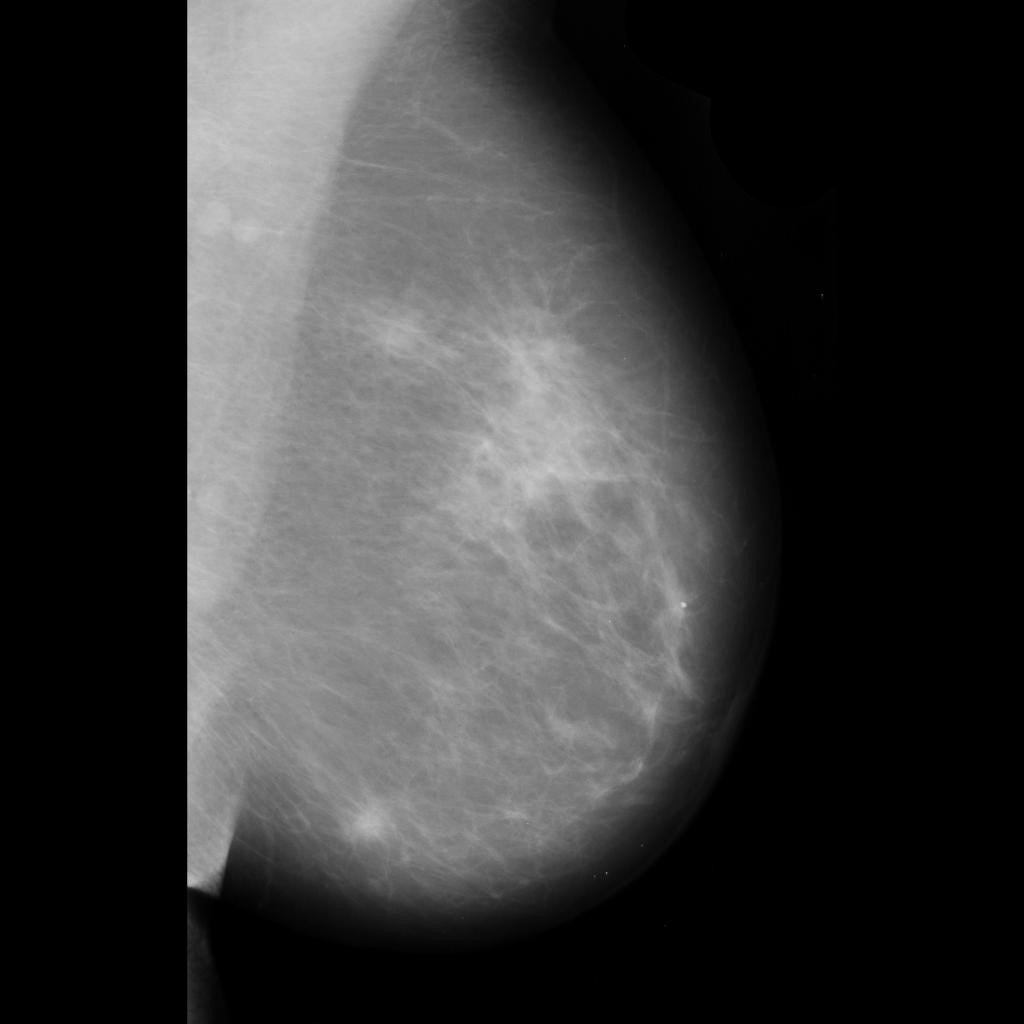

benign